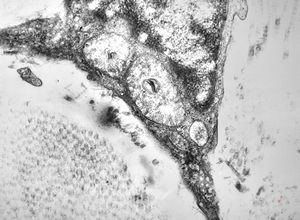

F, 46y. | verruca vulgaris … intranuclear virions

F, 46y. | verruca vulgaris … intranuclear virions

F, 46y. | verruca vulgaris … intranuclear virions